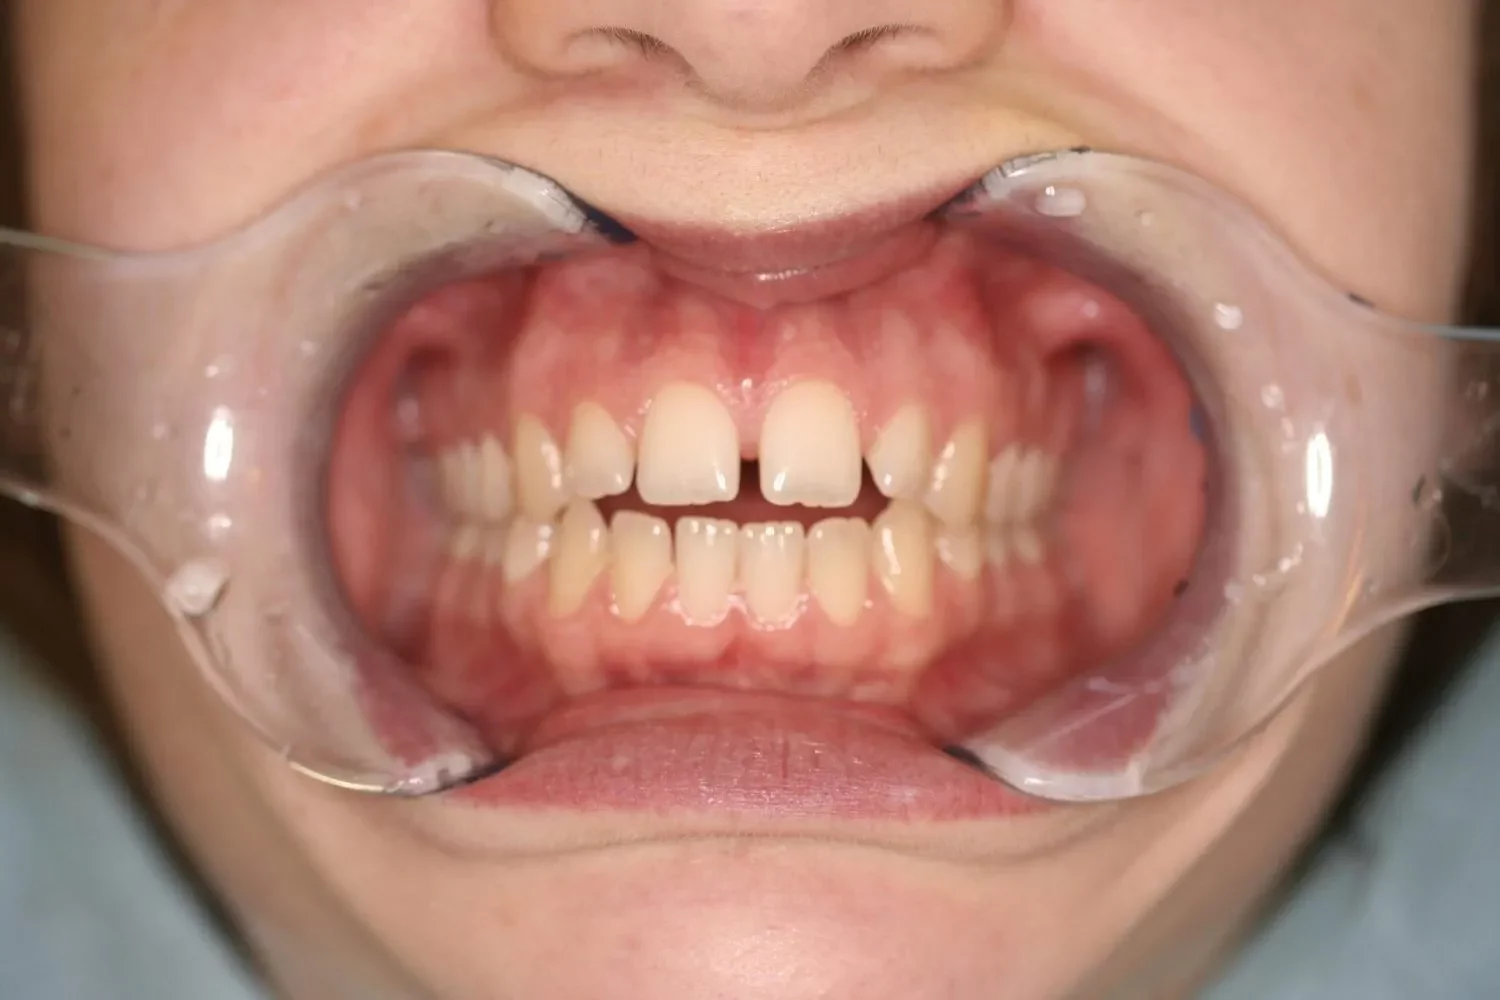

Invisalign Vergleich: Vorher-Nachher

Vorher-Bild einer Invisalign-BehandlungNachher-Bild der Invisalign-Behandlung